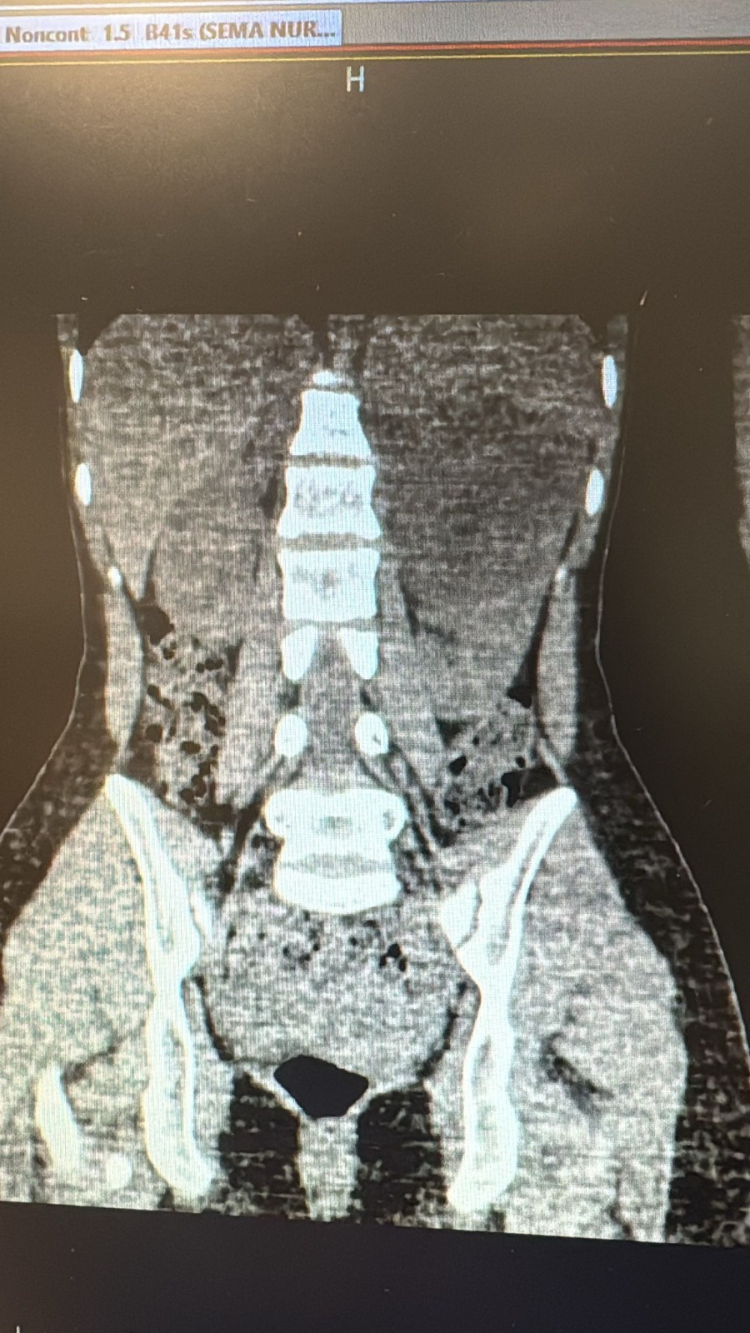

18 yaşında kadın hasta, uzun süredir devam eden sol yan ağrısı şikâyetiyle dış merkezde yapılan tetkikler sonucunda sol böbrekten kaynaklanan, yaklaşık 10 cm çapında ve böbreği ile dalağı iterek komşu organlara yapışıklık gösteren kist tespiti üzerine Viranşehir Devlet Hastanesi’ne yönlendirildi.

Hastanemizde yapılan gerekli tetkik ve muayenelerin ardından kistin cerrahi yöntemle çıkarılmasına karar verildi. Viranşehir Devlet Hastanesi’nde gerçekleştirilen başarılı ameliyatla, 10 cm boyutundaki böbrek kisti laparoskopik (kapalı) yöntemle, 2 adet 5 mm ve 1 adet 10 mm’lik kesi kullanılarak çıkarıldı. Bu sayede hastamız, büyük boyutlu kistine rağmen açık cerrahiye gerek kalmadan tedavi edilmiş oldu.